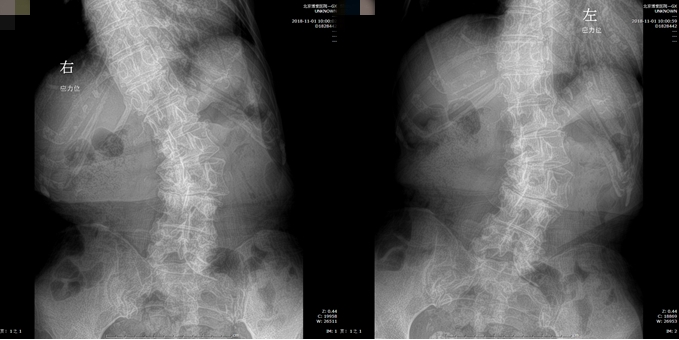

基本情况:女性,77岁,腰痛30年,加重一年,行走困难2月。身高158cm,体重190斤,就诊时轮椅推入病房。

影像检查:

洪毅教授:患者高龄,常年轻度慢性腰痛,本次加重1月余,无下肢神经功能损害,结合患者全长片、核磁体征表现,考虑患者疼痛加重原因为近期出现椎间关节损伤,需关注腰4-5,腰5-骶1节段。腰4-5小关节增生明显,椎间盘高度尚可,不能排除小关节骨关节病。腰5-骶1有ModicII期表现,可能为间盘源性疼痛来源,可进行诊断性封闭治疗。

孙常太教授:患者影像退变性骨关节病表现重,无椎管狭窄。虽有侧凸,但腰2-3,腰3-4侧弯节段可见明显的骨赘形成,稳定性强,腰5-骶1节段椎间盘高度已塌陷,亦较稳定,仅腰4-5节段仍有一定活动度,这就形成腰4-5节段的应力集中,体格检查压痛点与小关节位置亦吻合,需考虑重点关注此节段。

谭荣教授:同意孙教授意见,腰4-5节段动力位显示仍有一定活动度,同时腰4有I°滑脱,证明节段不稳定。病史中患者起身、刚下地时症状重亦支持节段不稳的表现。核磁腰4-5轴位可见明显的小关节病表现,Weishaup分级IV期,亦支持相关诊断。

王炳强教授:患者虽腰椎局部有不稳、侧弯、旋转等表现,但冠状位总体平衡尚可,矢状位有失平衡表现,可能为短期内疼痛加剧导致的,骨盆已参与代偿。若证实疼痛来源,手术完全可以仅进行短节段融合,顺应目前脊柱的形态,无需矫形纠偏等。